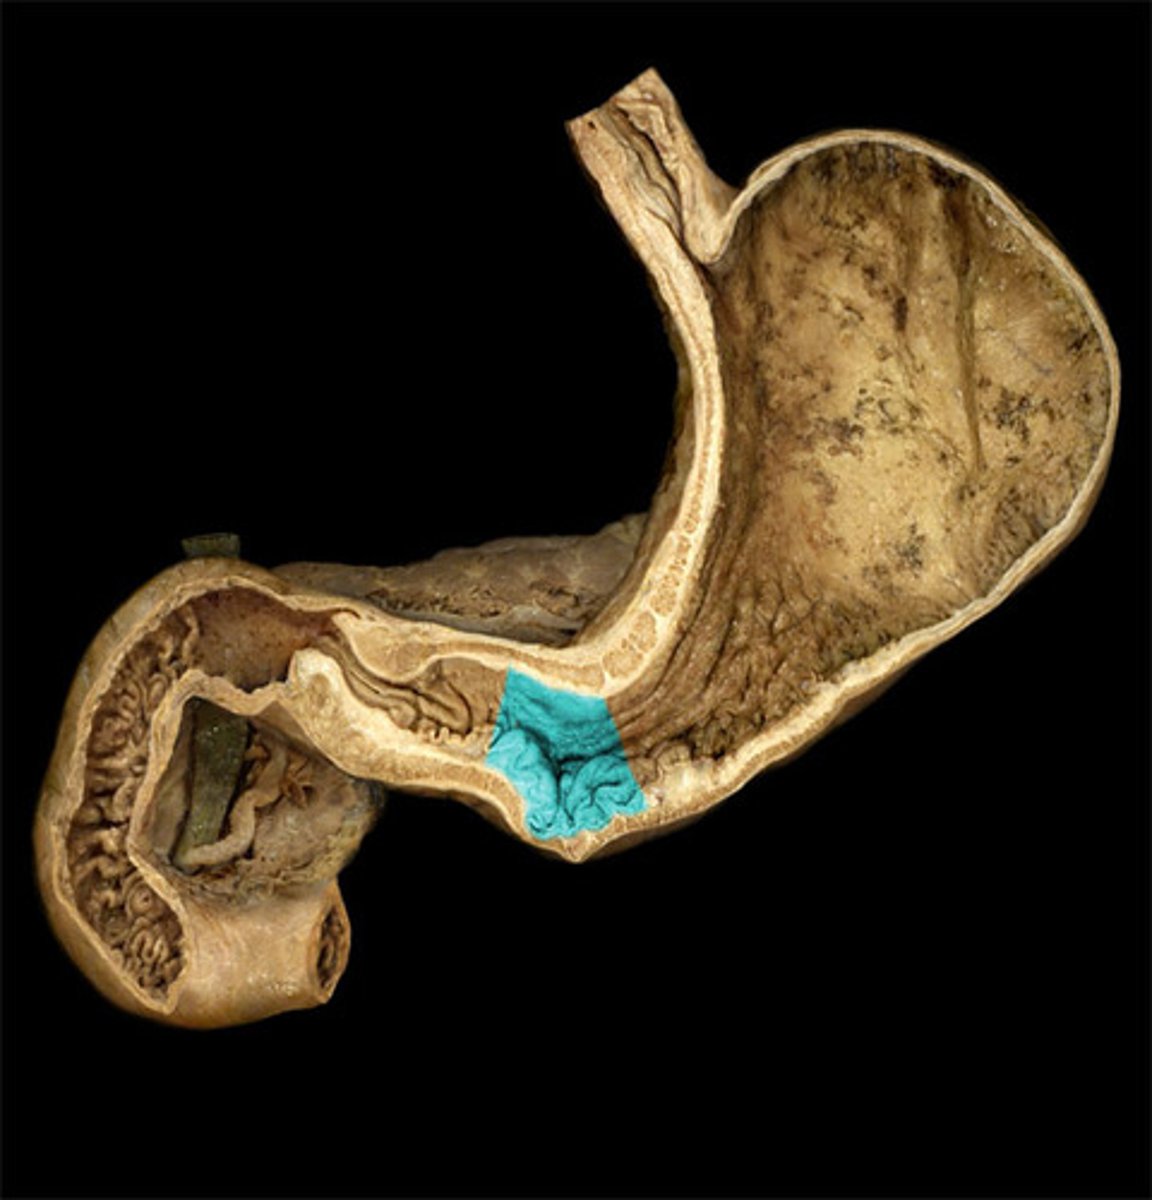

cardia

cardiac notch

fundus

body

greater curvature

lesser curvature

pyloric antrum

pyloric sphincter

gastric folds

major duodenal papilla

opening of ampulla into duodenum